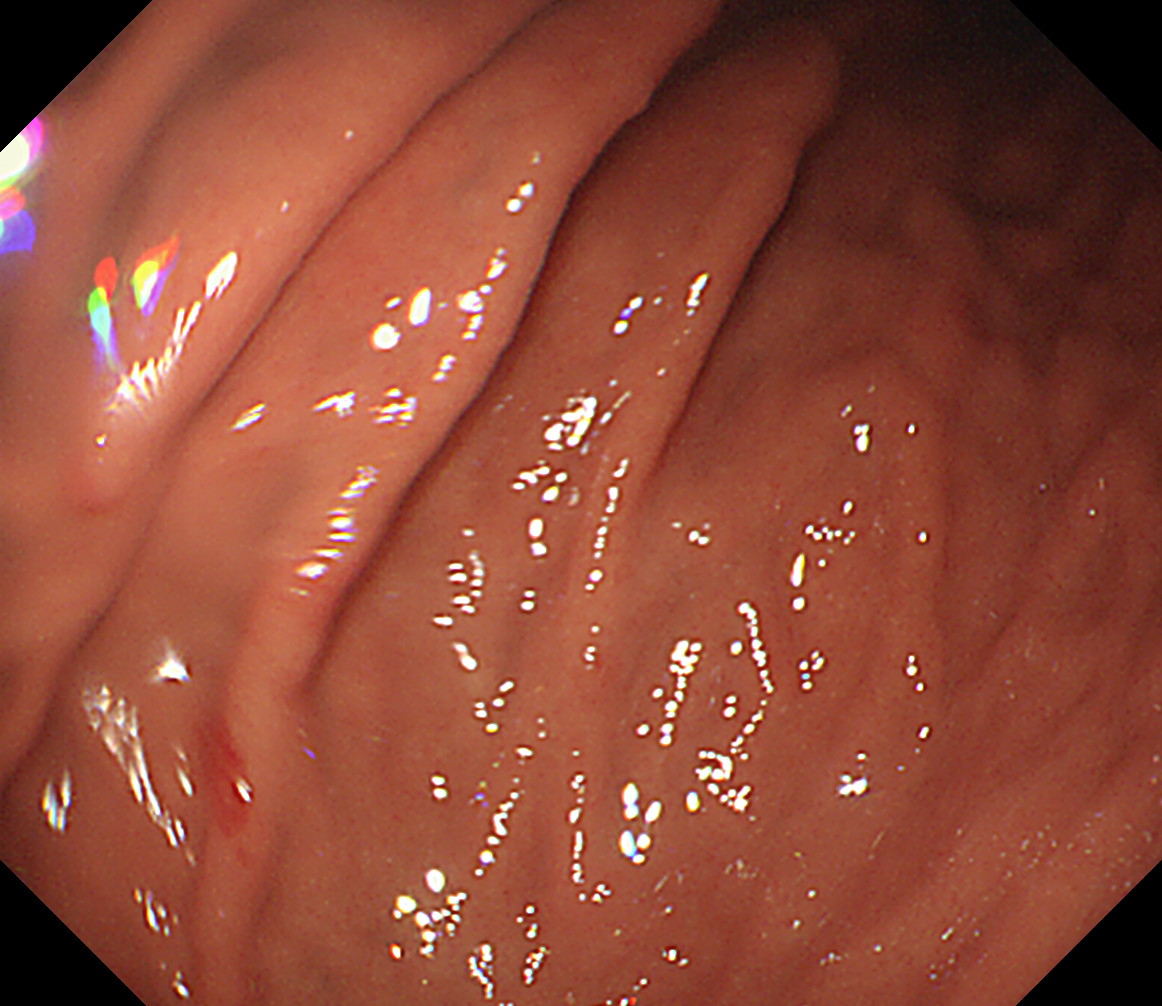

35 体上部大弯 エアーを十分入れて襞の間の病変を見逃さないようにする 体下部小弯